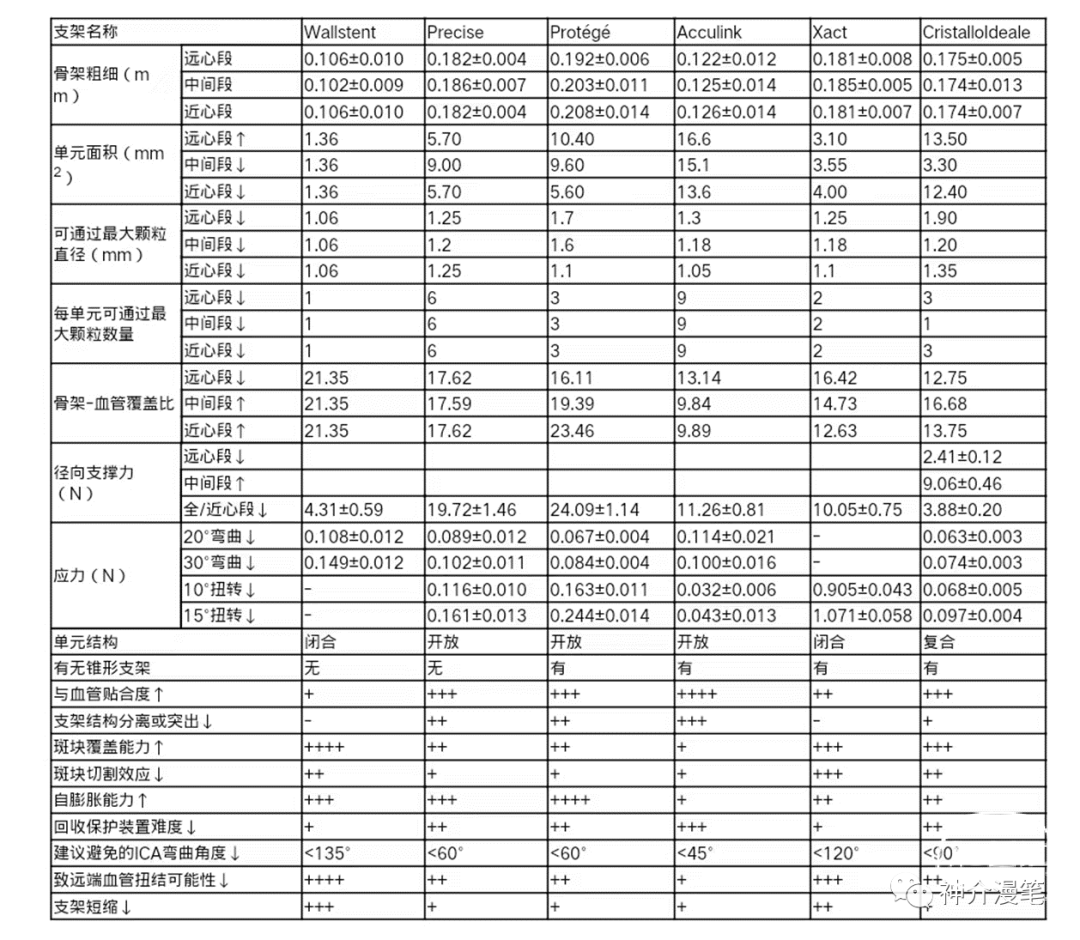

不同支架具有自己独特的特点,清楚地认识到各自的优缺点,才能更为精准的去选择,扬长避短,发挥最大的治疗效果。OK,接下来就简单分开介绍目前市场上的几大主流颈动脉支架,还是那句话,没有任何利益导向,纯学术探讨,而且更多的是个人理解,所以有不认同的,大家开诚布公的讨论,千万不要拍我的黑砖。

波科 WALLSTENT 支架

Wallstent支架不同于前面两款,自身特点同样突出,关键词:编织支架,闭环支架,自膨支架,是目前主流颈动脉支架中唯一一款编织支架。具备着编织支架普遍共性,在不同管径血管内会被拉伸和短缩,释放难度略高于其他几款支架,但是有更高的金属覆盖率和更小的网眼面积。此外,wallstent支架的显影性是最棒的,这一点用过的可能都知道。

需要提醒大家注意的是,编织支架在不同管径的血管中会出现明显长度的变化,如下表所示。因此选择支架长度时一定要根据目标血管直径来选择合适长度的支架,避免过长或过短,另外wallstent支架释放后会有一定程度的回缩,所以定位支架着陆点时应预留足够测长度,防止支架短缩后无法完全覆盖狭窄造成尴尬的局面。另外需要注意的是,wallstent支架和所有闭环支架一样,在释放时需远端打开一定长度后方能彻底打开贴壁,在此过程中如后手把持的力度不够有可能造成支架下滑。

最后来一个汇总图吧,把所有支架的参数放在一起,大家一块比一比,这样心中就都有数了。